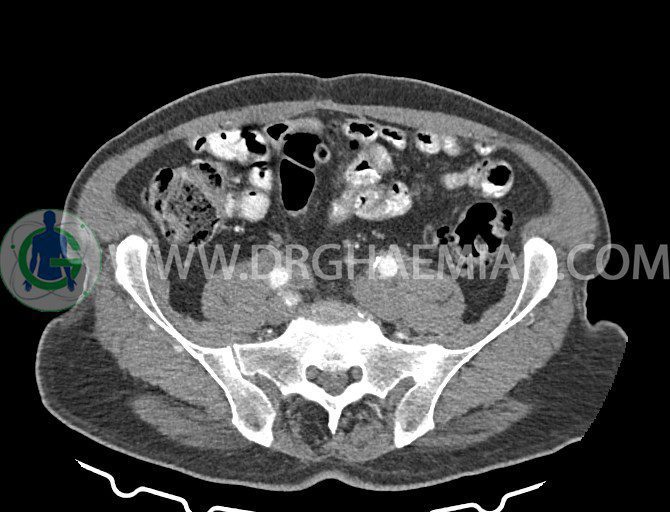

سی تی اسکن لگن یکی از روش های تصویربرداری با سی تی اسکن است. این روش با استفاده از تشعشعات تصاویر عرضی از ناحیه شکمی ایجاد میکند. در این کیس ديورتيكولوزيس، کیست های کورتیکال در هر دو کلیه، لنفادنوپاتی، کلسیفیکاسیون دیواره آئورت و شریان ایلیاک، تغییرات DJD ناحیه توراکولومبار و پروستات بزرگتر از عادی دیده می شود.

در سي تي اسکن اسپيرال شکم و لگن با و بدون کنتراست خوراکی و وريدی (مولتي ديدکتور 16 با مقاطع ظريف و بازسازي هاي ساژيتال و کرونال):

– کلسيفيکاسيون ديواره آئورت و شريان ها ايلياک همراه با نشانه هاي ترومبوز مورال در بيفورکاسيون ائورت با امتداد به پروگزيمال هاي شريان هاي ايلياک

لنفادنوپاتي به ابعاد mm 22 x 25 مجاور شريان ايلياک خارجي چپ و به ابعاد mm 17 x 28 مجاور شريان ايلياک خارجي راست

– پروستات به ابعاد mm 45 x 54، بزرگ تر از نرمال

مشهود است.

– مطابقت سونولوژيک و بررسي بافتي لنفادنوپاتي پيشنهاد مي شود . (sono guided CNB)